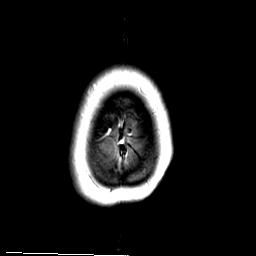

MR Study #3 -- Slice #50